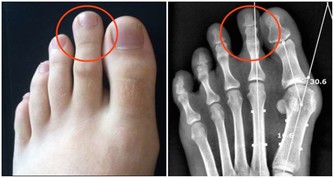

進入老年後,人體肌肉會減少3%-5%,關節開始退化,上下樓梯或者爬山時,

膝關節承受人體重量是平時的3-5倍,這會加重關節老化。